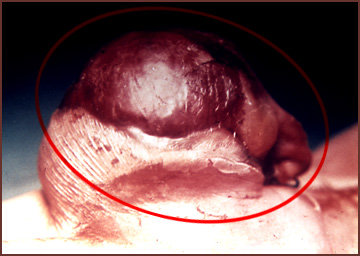

Onfalocele

Defecto de cierre de la pared abdominal, que deja expuesta en el liquido amniótico al intestino. La imagen operatoria muestra el aspecto acartonado del intestino, macerado por el liquido amniótico (círculo rojo).